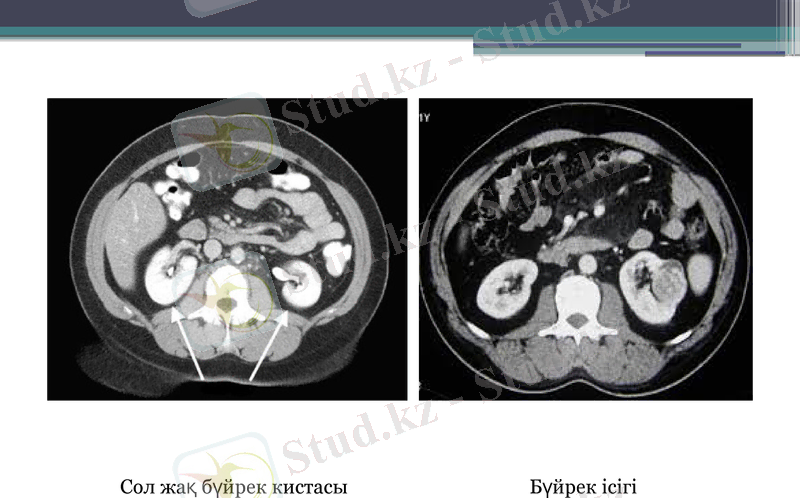

КТ

Қалыпты КТ зерттеу кезінде бүйректердің үш деңгейін : жоғарғы полюсін, қақпалар деңгейін жіне төменгі полюсін саралайды. Томограммаларда полюстер контурлары біркелкі анық, овал түріндегі құрылымдарда көрінеді. Бүйректер май клеткамен қоршалған себепті клетчатка фонында жақсы анықталады. Бүйректер талшықты қабықпен қапталған, қалыптыда көрінбейді. Талшықты қабықтан қабықтан сыртқа қарай май капсуласын құрайтын қабаты болады. Май капсуладан тысқары бүйрек шандыры, оның алдыңғы және артқы қабықшасы орналасады.

Сол жақ бүйрек кистасы

Бүйрек ісігі